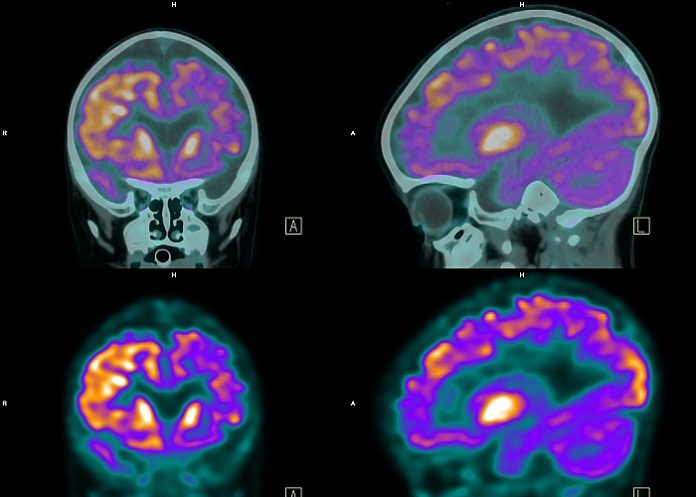

The age of symptom onset in sporadic Alzheimer’s is strongly correlated with the age that an individual reaches a tipping point in amyloid accumulation in the brain, measured in a PET scan, found a study in Neurology. An algorithm yields an estimate of how far a person has progressed toward dementia and how much time is left before cognitive impairment sets in.

Researchers at Washington University School of Medicine in St Louis have developed an algorithm-based approach, using data from a kind of brain scan known as amyloid positron emission tomography (PET) to gauge brain levels of the key Alzheimer's protein amyloid beta.

In those who eventually develop Alzheimer's dementia, amyloid silently builds up in the brain for up to two decades before the first signs of confusion and forgetfulness appear. Amyloid PET scans already are used widely in Alzheimer's research, and this algorithm represents a new way of analysing such scans to approximate when symptoms will arise. Using a person's age and data from a single amyloid PET scan, the algorithm yields an estimate of how far a person has progressed toward dementia and how much time is left before cognitive impairment sets in.

The researchers applied a widely used metric known as the standard uptake value ratio (SUVR) to the scans to estimate the amount of amyloid in each participant's brain at each time point. They also accessed more than 1,300 clinical assessments on 180 of the participants. The assessments typically were performed every one to three years. Most participants were cognitively normal at the start of data collection, so the repeated assessments allowed the researchers to pinpoint when each participant's cognitive skills began to slip.

Brain amyloid burden was measured by amyloid PET with Pittsburgh compound B. The mean cortical standardised uptake value ratio (SUVR) was transformed into a timescale using longitudinal data.

Amyloid accumulation was evaluated in 236 individuals who underwent more than one amyloid PET scan. The average age was 66.5 ± 9.2 years and twelve individuals (5%) had cognitive impairment at their baseline amyloid PET scan. A tipping point in amyloid accumulation was identified at a low level of amyloid burden (SUVR 1.2), after which nearly all individuals accumulated amyloid at a relatively consistent rate until reaching a high level of amyloid burden (SUVR 3.0). The average time between levels of amyloid burden was used to estimate the age at which an individual reached SUVR 1.2. Longitudinal clinical diagnoses for 180 individuals were aligned by the estimated age at SUVR 1.2. In the twenty-two individuals who progressed from cognitively normal to a typical AD dementia syndrome, the estimated age at which an individual reached SUVR 1.2 predicted the age at symptom onset (R2=0.54, p<0.0001, root mean square error (RMSE) 4.5 years); the model was more accurate after exclusion of three likely misdiagnoses (R2=0.84, p<0.0001, RMSE of 2.8 years).